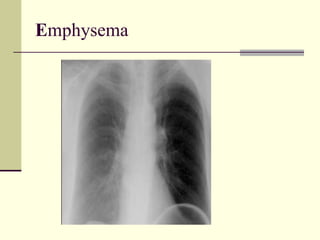

EMPHYSEMA Alpha 1 Anti-Trypsin Deficiency Hyperinflation Hyperlucency  Low set flat diaphragm  Vertical heart  Pre and infra cardiac lungs  Barrel shape  Emphysema Avascular zones  Cephalization of upper lung fields is not evident  Predominant basal involvement (not evident)

EMPHYSEMA Alpha 1Anti-Trypsin Deficiency Hyperinflation Hyperlucency Low set flat diaphragm Vertical heart Pre and infra cardiac lungs Barrel shape Emphysema Avascular zones Cephalization of upper lung fields is not evident Predominant basal involvement (not evident)